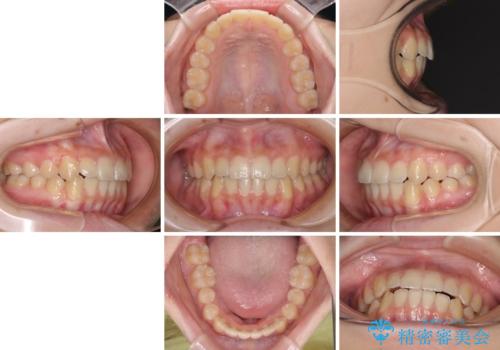

前歯のクロスバイト メタル装置での矯正治療

- 前歯のクロスバイトを気にして来院された患者様です。

前歯の叢生を解消するスペースを獲得するために上顎左右の親知らずを抜歯し、メタルブラケットにて矯正治療を行うこととしました。

当初は1年半程度の治療期間を想定していましたが、上下の正中を合わせていく過程で奥歯の咬みにくさが続いてしまい、2年以上の治療期間を要することとなりました。